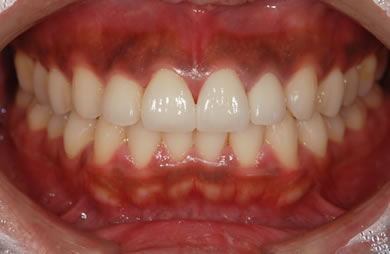

| 性別/年齢 | 男性 / 29歳 | ||||||||||||||||||||||||||||||||

| 主訴 | 歯並びを綺麗にしたい。奥歯の銀歯が目立つので白くしたい。 | ||||||||||||||||||||||||||||||||

| 治療方針 | 上の前歯部に関しては審美的回復の優先を切望されているため、透明感のあるオールセラミックのハイクオリティタイプを使用。 | ||||||||||||||||||||||||||||||||

| 治療内容 | オールセラミック(ハイクオリティ)3本、ハイブリッドセラミックインレー10本 | ||||||||||||||||||||||||||||||||

| 総治療費 | 714,286円 | ||||||||||||||||||||||||||||||||

| 治療期間 | 7ヶ月 |